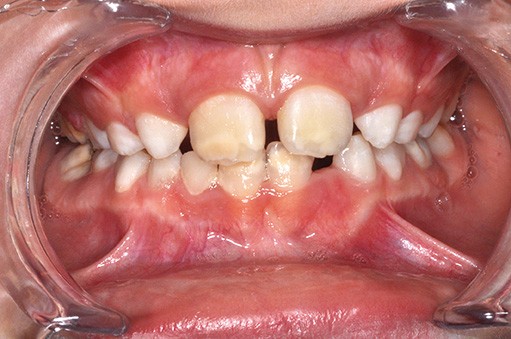

Après l’intervention de Caroline Delfosse, MCU-PH en odontologie pédiatrique à Lille, sur les aspects particuliers de la relation de soin avec l’adolescent, Jean-Pierre Attal, MCU-PH à Paris Descartes, abordera la question très actuelle de l’érosion-infiltration. Cette technique, initialement développée pour stopper le processus carieux dans les secteurs postérieurs, trouve des indications dans la prise en charge des défauts esthétiques antérieurs (white spot, fluorose, dyschromies post-traumatiques). Il présentera également de nouvelles propositions thérapeutiques permettant de traiter les cas de MIH antérieurs qui sont souvent à l’origine de demandes esthétiques fortes (fig. 2).